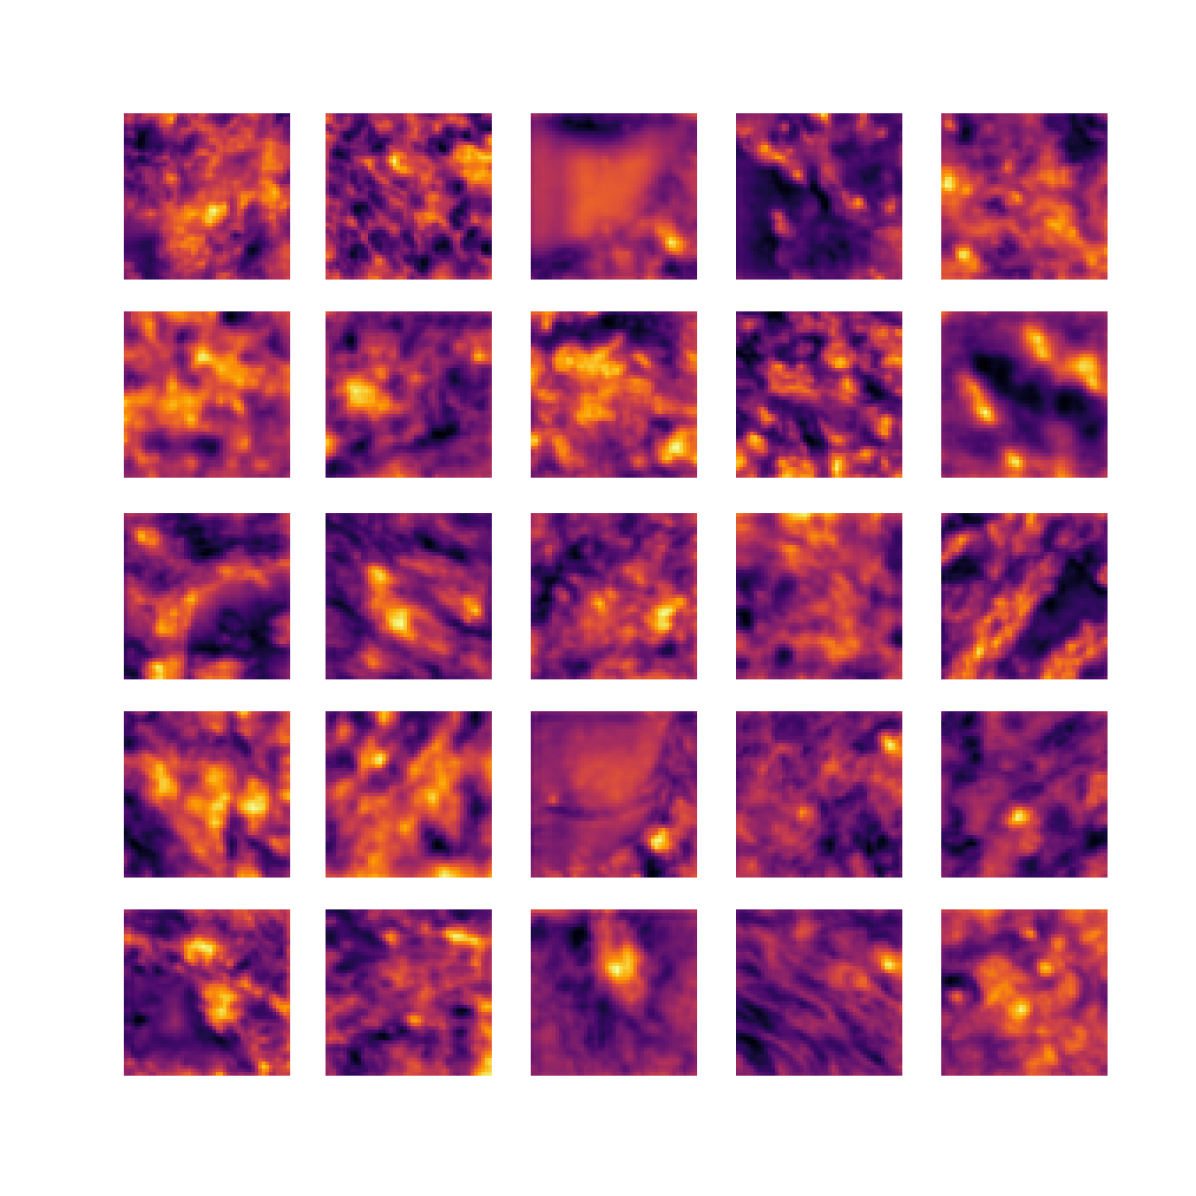

We also analyse the activation maps for each model using GradCAM as described in section S3. This offers more insight into the areas of the image which are contributing most heavily to the models’ representations. In Figure 4(b) we present some representative examples, however, a larger selection which was chosen at random is presented in Figures S10 to S25. The larger selection makes it easier to see the emergent patterns, including that privileged Siamese models tend to mainly identify features which are strongly present in both inputs, while unprivileged Siamese models tend to learn more diffuse features that are not specific to one cell phenotype or image region. TriDeNT ♆ incorporates both sets of features, learning both features specific to the privileged data and more the general features associated with unprivileged Siamese networks.

We can see in Figure 4(b) panel A that for ERG, the privileged Siamese model focuses almost exclusively on any nuclei which could be endothelial cells. As there are very few endothelial cells in the dataset, it could be an effective strategy to identify anything that could potentially be an endothelial cell to minimise the difference between the representations of the H&E model and the IF mask model. In the corresponding unprivileged Siamese image, we see that the model identifies some of these nuclei, albeit less strongly, but also focuses heavily on the other tissue and even the background, while strongly fixating on two spots of debris in the center of the image. This model has less ‘incentive’ to learn the weak features related to endothelial cells as these occur rarely and are not easy to detect, while more generic strong features such as the presence of connective tissue and the prevalence of background are more common and predictable from augmented images. We see that TriDeNT ♆ combines these two feature sets, strongly identifying nuclei while also identifying the connective tissue.

In panel C we see a similar pattern, with the privileged Siamese model fixating solely on the nuclei, while the TriDeNT ♆ model takes a more balanced approach. The unprivileged Siamese model appears to focus on a single cluster of nuclei while neglecting others, and similarly identifies an area of fibroblasts with its distinctive pattern but does not others.

In contrast to panels A and C which represent models with poor privileged Siamese results, panels B and D represent models whose privileged Siamese results were comparable to both TriDeNT ♆ and even the supervised baseline. It is therefore interesting to note that there are far more similarities between the privileged Siamese and TriDeNT ♆ models in both cases. Particularly in panel B, TriDeNT ♆ and the privileged Siamese model return virtually identical heatmaps, with both strongly identifying epithelial nuclei and neglecting the same areas of connective tissue. The unprivileged model in this case appears to focus solely on the centre of the image, giving a significantly different heatmap to the other panels.

Panel D again shows the previous pattern, with the privileged Siamese model identifying the features strongly present in the privileged data – fibroblasts – while neglecting the nuclei present. TriDeNT ♆ also strongly identifies the connective tissue, but, unlike the privileged Siamese model, does not completely neglect the nuclei. The unprivileged Siamese model primarily identifies background, and does not appear to identify the nuclei in this example.